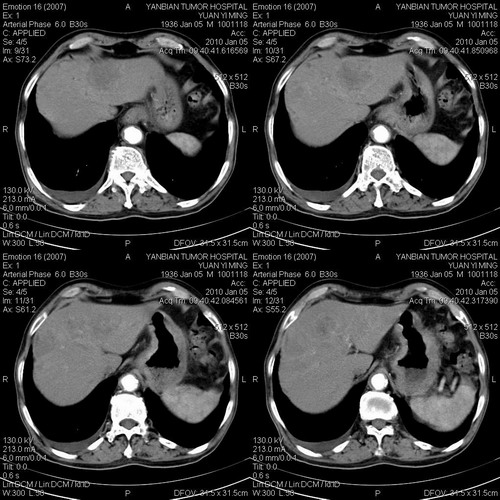

标题: CT24024:男,74岁。体检超声发现肝内多发占位性病变四天。 [打印本页]

标题: CT24024:男,74岁。体检超声发现肝内多发占位性病变四天。

肝癌肝内转移,胃壁增厚,胃癌不能排除

建议查afp。考虑多发结节型肝癌。

考虑多发结节性肝癌。

1)考虑肝脏恶性肿瘤(转移瘤?)。2)肝外胆管轻度扩张。3)左肾小囊肿。